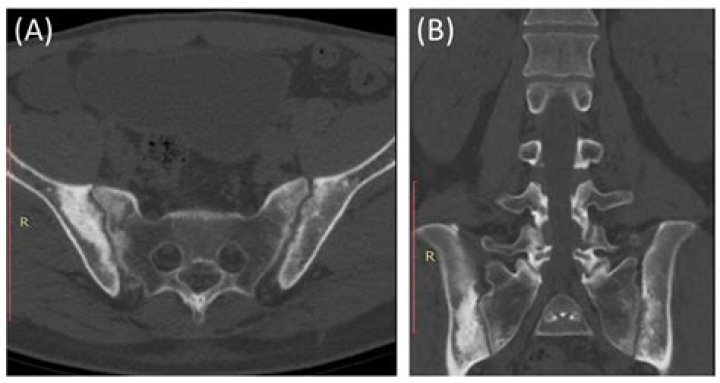

Will a CT scan show sacroiliitis?

This study showed that abdominal CT can establish a diagnosis of structural sacroiliitis with the same level of sensitivity but with a higher specificity (100%) than pelvic plain radiography.